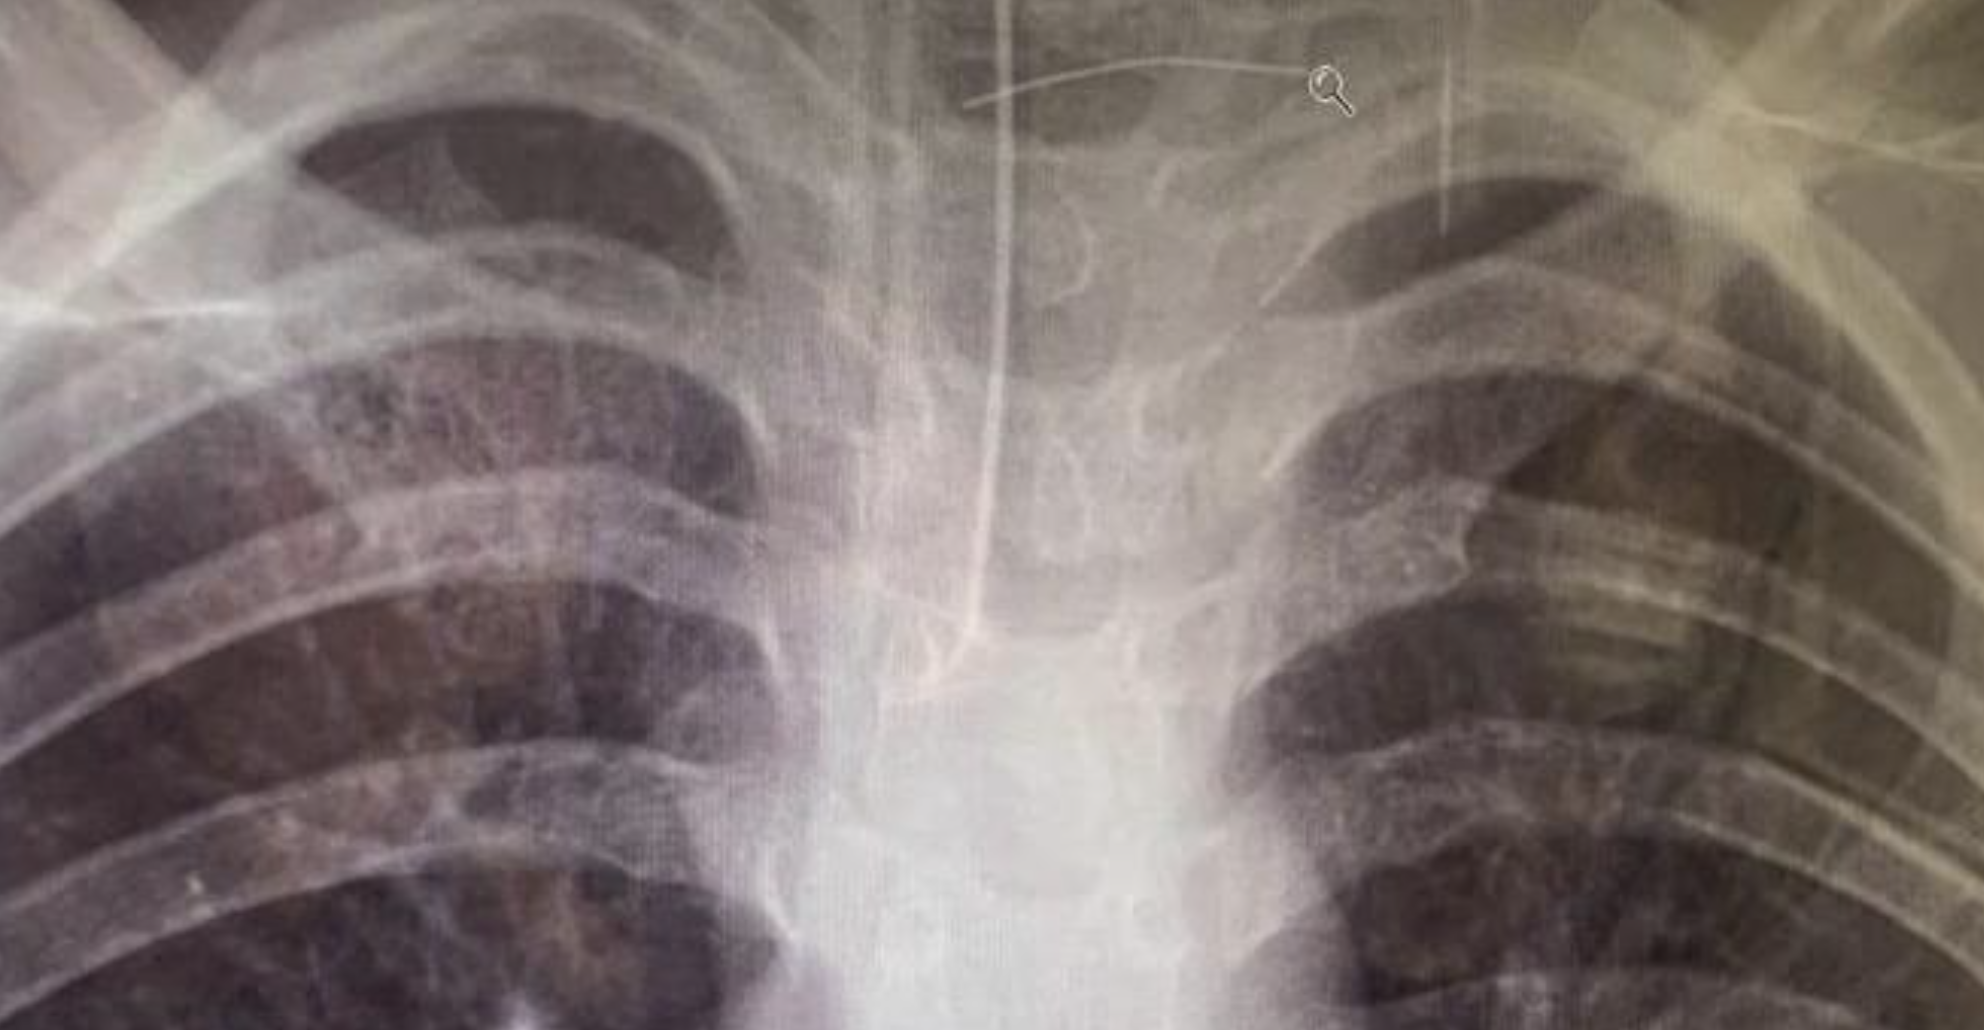

All’arrivo in ospedale, i medici hanno immediatamente notato che la bambina era disorientata e non riconosceva nemmeno i suoi genitori e parenti. I sintomi mostravano una gravità che sembrava non collegata al panino mangiato giorni prima. Le indagini radiografiche hanno rivelato la presenza di ascessi cerebrali, causati da un’infezione scatenata dalla setola ingerita.

La setola, oltre a provocare il mal di gola e una febbre alta, aveva perforato l’esofago, affrontando un percorso pericoloso fino all’arteria carotide. La situazione ha richiesto un trasferimento d’urgenza in un centro pediatrico a Sydney, dove sono state eseguite le cure necessarie per il recupero della sua salute. Fortunatamente, la bimba ha risposto bene alle terapie e, sebbene continui a ricevere assistenza medica, è tornata finalmente a casa.